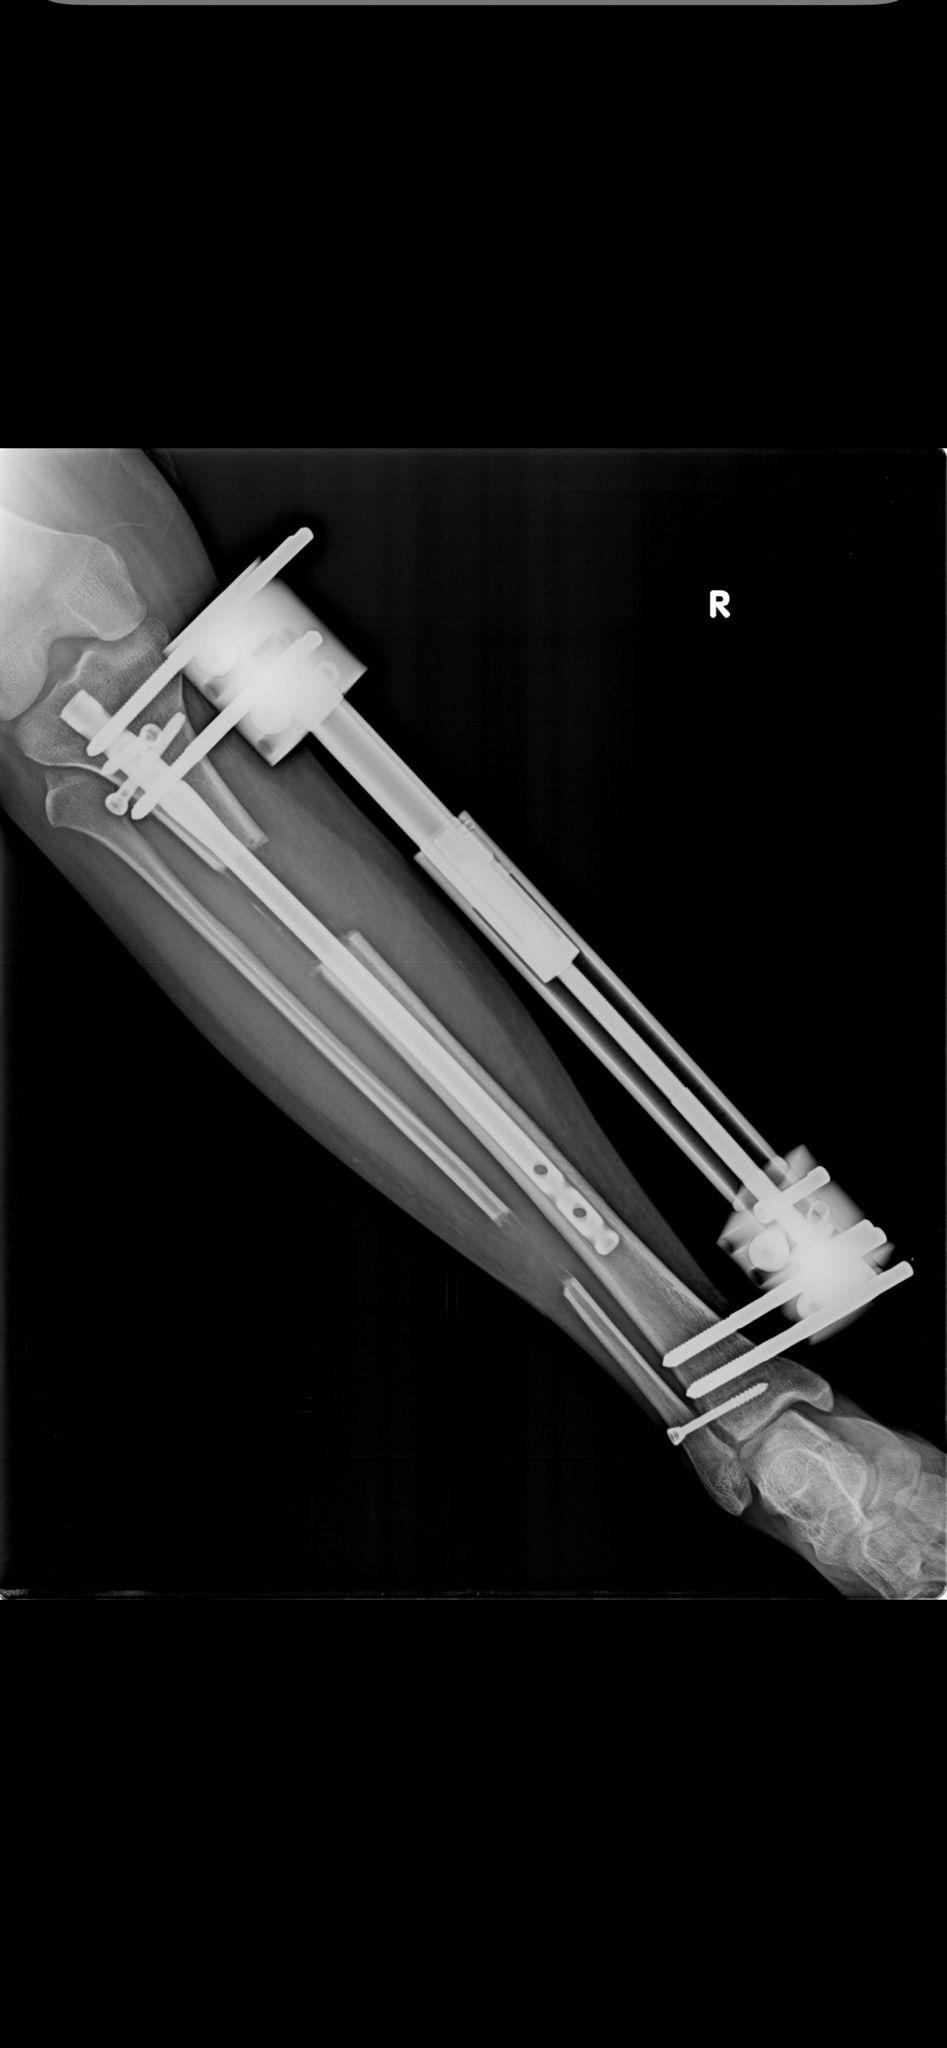

Yöntem ve Röntgen Görüntülerimiz

BAŞARILI SONUÇLARIMIZ

Boy uzatma ameliyatlarımızda kullandığımız modern yöntemlerin röntgen görüntüleri ve başarılı sonuçlarımızı inceleyebilirsiniz.

Fitbone Yöntemi

Fitbone® Yöntemi ile Boy Uzatma Tamamen İçten (Internal) Motorize Uzuv Uzatma Teknolojisi